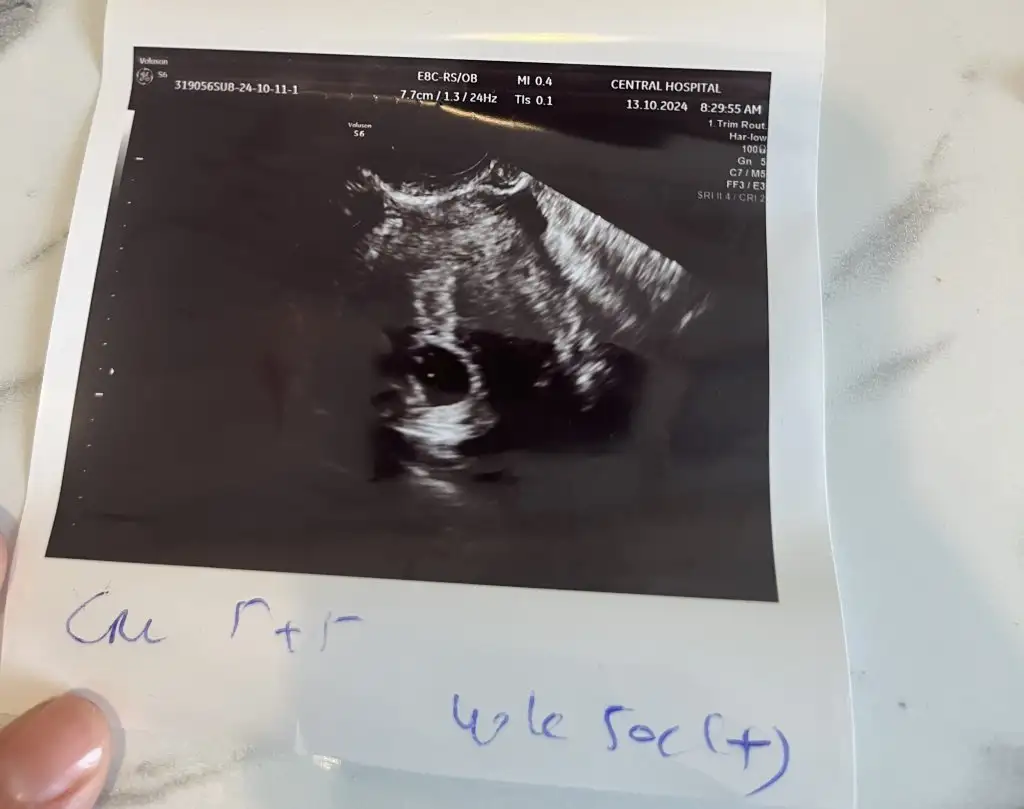

Canım benim ilk iki gebeliğimdede geç duyulmuştu 7+2 gibi sanırım, geç döllenme olabiliyor bazen daha yavaş başlaya biliyor , bazen cihazda sorun oluyor çok eski model oluyor. Endişe etme, bir kaç güne belli olur. Kendi doktoruna gidersin hafta sonu rahatlarsın. Ultrason kağıdına da baktım çok bilgi yok yani ölçü orda alınmamış yada belirtilmemiş ama kese vs gözüküyor dert etmeHanımlar selamlar.kendi doktorum bu cuma için randevu vermişti. Ben ise yine sabredemeyip başka bir doktora gittim bu günçok şükür bebeği ve yolk kesesini gördük.ancak kalp atışını ne gördük ne duyduk.bi moralim bozuldu yani 7 haftadayım duyulması gerekmezmiydi ?

Ay bi bakabilirseniz çok sevinirim.Öyle bişey olsa Allah korusun doktorlar bu tarz şeyleri gizlemiyor direk yüzüne söylüyor çatır çatır yani bana öyle yapmıştı kese boyutu falan normal demekki boyu kaç ultrason görüntünü at istersen bi